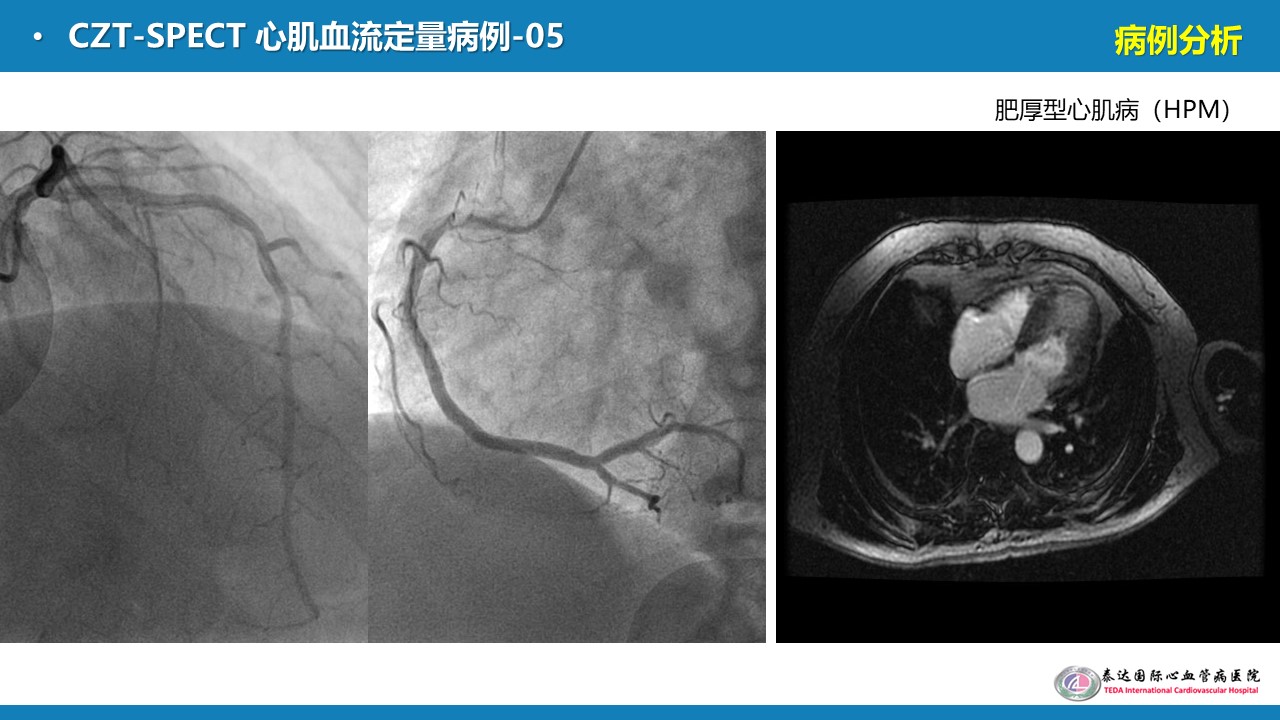

【核汇园】之(85)- 李剑明教授讲授《CZT心脏SPECT临床研究及进展》